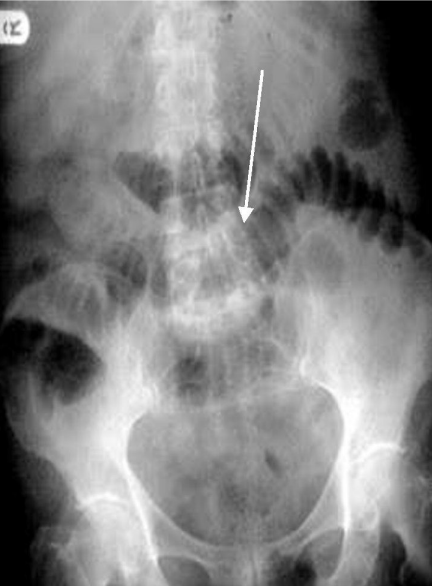

Homem, 63 anos. Dor abdominal em cólica, náusea e vômitos escuros há 24h. Passado de retosigmoidectomia aberta por doença diverticular há 4 anos. Traz o Rx abaixo.

Assinale a alternativa CORRETA em relação ao caso.